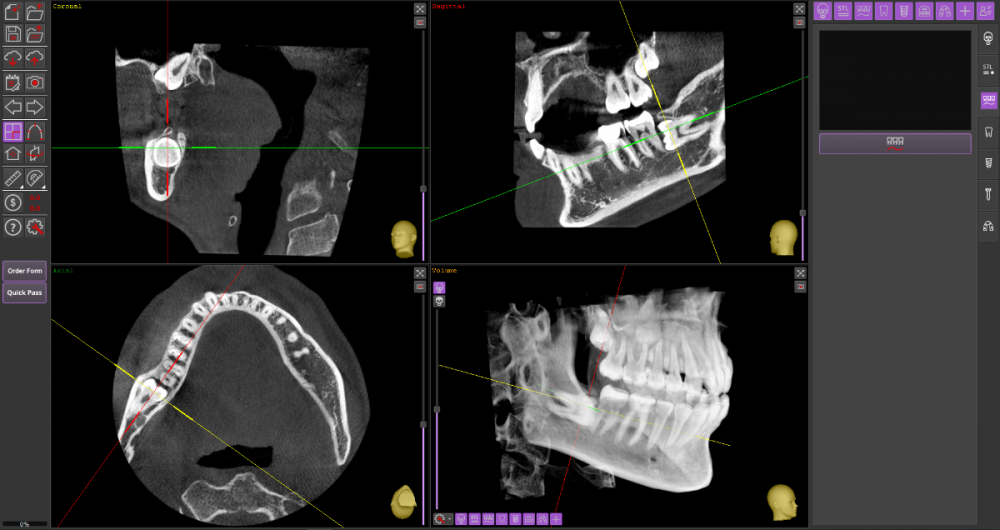

Прошу Вашего совета по поводу удаления восьмых зубов.

Из жалоб есть непродолжительная ноющая боль в правой нижней челюсти, не связанная с внешними раздражителями.

1. Необходимо ли удаление зубов мудрости?

2. Возможно ли удаление амбулаторно, без общего наркоза?

3. Нет ли риска для семёрок при удалении.

18_1.thumb.png.d91054e49b28268758a599090ae03866.png

18_2.thumb.png.c2485df9a2914bfd93a60f7a391f45d0.png

Виновником боли в н.ч. справа может быть, например зуб 46, не только 48.

1. Удаление 8-х зубов скорее всего необходимо

2. Удаление амбулаторно вполне возможно. Общая анестезия (наркоз) совершенно необязательна, местной анестезии достаточно.

3. Несчастные случаи бывают, но крайне редко.